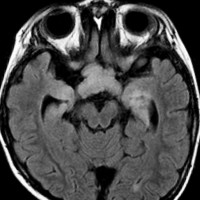

whole optic pathway pilocytic astrocytomaとは

両側の眼窩内視神経から視交叉、視索,外側膝状体,内包後脚,視放線近位部までが腫瘍化しています。FLAIRで高信号で,不規則にガドリニウム増強されます。これを手術摘出したり生検したりしても無駄です。放射線治療は不可能であり治療方法は化学療法のみです。

この子はCDDP/VCRの化学療法から開始して12年になりますが,今は無治療でわずかな視力ですが学校に通っています。優等生です。自然退縮を見ていますが,今後も変化する可能性はすこし残しています。